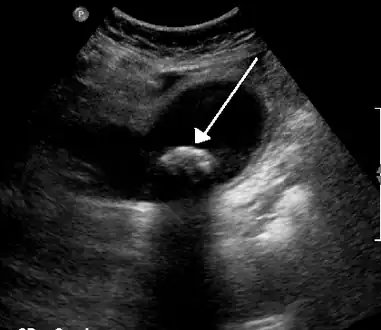

| Biliary colic is often related to a stone in the gallbladder | |

Diagnosis is guided by the person's presenting symptoms and laboratory findings. The gold standard imaging modality for the presence of gallstones is ultrasound of the right upper quadrant. There are many reasons for this choice, including no exposure to radiation, low cost, and availability in city, urban, and rural hospitals. Gallstones are detected with a specificity and sensitivity of greater than 95% with ultrasound.[18] Further signs on ultrasound may suggest cholecystitis or choledocholithiasis.[12] Computed Tomography (CT) is not indicated when investigating for gallbladder disease as 60% of stones are not radiopaque.[12] CT should only be utilized if other intra-abdominal pathology exists or the diagnosis is uncertain.[19] Endoscopic retrograde cholangiopancreatography (ERCP) should be used only if lab tests suggest the existence of a gallstone in the bile duct.[12] ERCP is then both diagnostic and therapeutic.